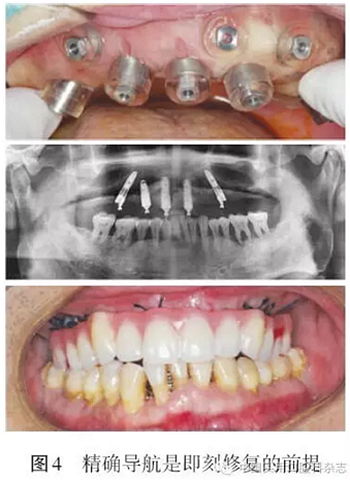

同全口種植固定義齒修復設計流程大致相同,但All-on-4術(shù)式多采用即刻修復即刻負重。因此在制作放射性導板時,應同時制作過渡性義齒。在種植設計過程中,應利用傾斜種植體最大限度的延展近遠中向長度,減少游離端懸臂的長度。在設計后牙區(qū)傾斜種植體時,要充分考慮上頜竇前壁、頦孔等重要解剖結(jié)構(gòu),同時要注意合適的角度基臺的選擇,保證即刻修復能夠?qū)崿F(xiàn)(圖3~4)。